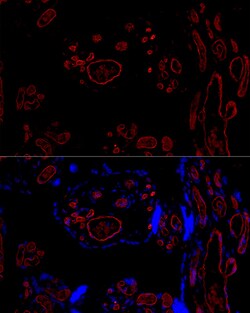

| ELISA, Immunohistochemistry (Paraffin), Western Blot, Immunocytochemistry | |